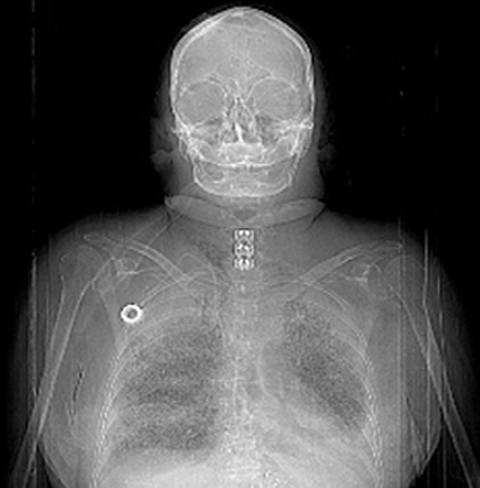

Above is the scout film (plain PA radiograph taken to indicate which sections are taken on a CT scan) of the person on Table 3-5. Note the metal plate in the lower neck. Also note the chemo infusion port or VAD (vascular access device) on the right chest wall, threaded down into the right atrium. A VAD is often used for chemotherapy.

On the CT scan below, scroll down to the fixation plate in the neck of the same person (between 40-45 on the time scale, located at approximately L9).